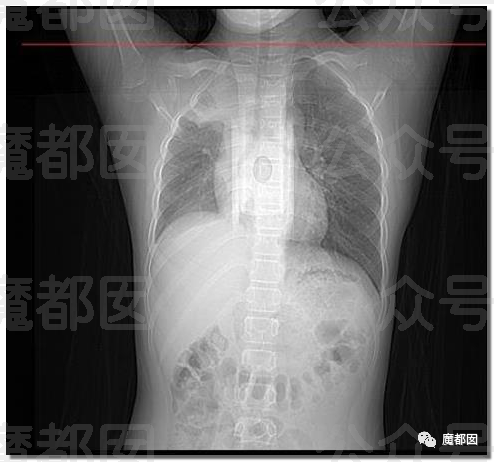

我们都晓得,正常情况下肺部是由肺泡组成的,肺泡里边是充满了空气的,进行CT或者是X线检查的时候,射线穿过肺泡的时候,影像的表现应该是黑色的区域,但是当肺泡里边出现炎症和感染,有渗出液和炎性细胞的时候,肺泡就被这些渗出液或者炎性细胞填充,这样射线就穿不透,在影像学上的表现就出现了白色的区域,这个白色区域反映出来的是渗出物的影像学的表现。

随着这些渗出液的吸收、炎症的消退,白肺的表现也会逐渐消退,也就是说肺部的影像学表现就会回到正常的黑色的区域。并不是只要肺部出现了炎症就都叫白肺,比较严重的肺炎的表现才会出现白肺,一般来讲肺部的炎症比较重,渗出比较多的时候,就是白色的影像区域面积达到了70%到80%的时候,才在临床上把它称为白肺。